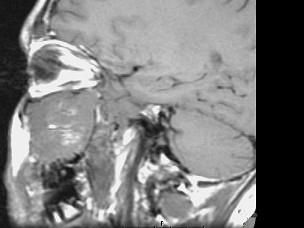

问题 15岁,男性,渐进性鼻塞1年余,MRI扫描如图所示,请选择最可能诊断 ( )

选项 A、鼻咽部囊肿 B、鼻咽癌 C、鼻咽部脓肿 D、脊索瘤 E、鼻咽部纤维血管瘤

答案 E